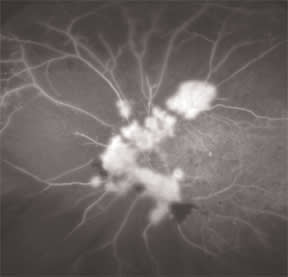

We had one patient with some hemorrhaging, showing neovascularization and tremendous capillary dropout. The wider view (Figure 2) delineated the extent of the disease and helped me decide if I should photocoagulate out into the healthy retina or simply treat the areas of ischemia. Another patient had a few small laser spots and macular edema. The wide view allowed me to see some extensive peripheral capillary dropout that otherwise could have gone undetected.

Figure 2. A wider view delineated the extent of the disease in this patient with hemorrhaging, neovascularization and capillary dropout.